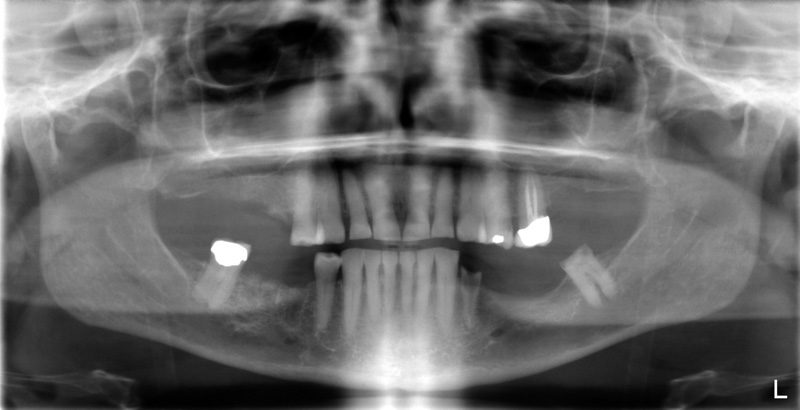

Pre X-Ray

Post X-Ray